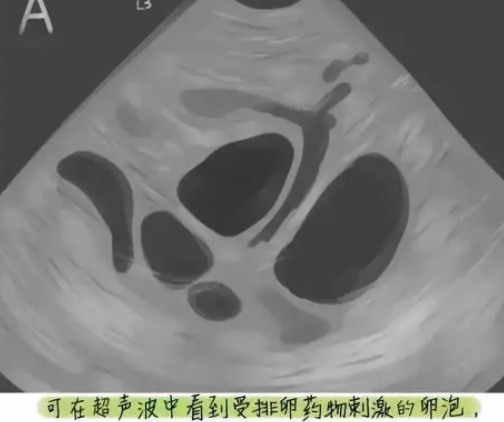

一般情况下,女性每月只排出一个卵子,没有足够的营养可以使其他卵泡发育成熟,从而走向衰败。临床上为提高卵子的使用率,会用一定量的药物给卵子足够的营养,使本来要凋亡的卵子,能够继续生长。

促排卵过程中通过B超监测卵泡生长情况结合激素变化调整促排卵药物,当卵泡发育成熟后给予扳机药物诱导卵母细胞成熟,一般在药物扳机后36小时行取卵术。